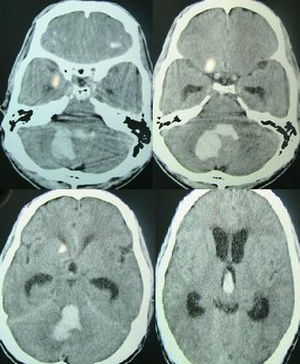

- Head CT (non-contrast)

- CT required as it is often clinically indistinguishable from SAH, ischemic stroke

- Findings dictated by location of bleed (in order of most common)

- Putamen

- Thalamus

- Pons

- Cerebellum